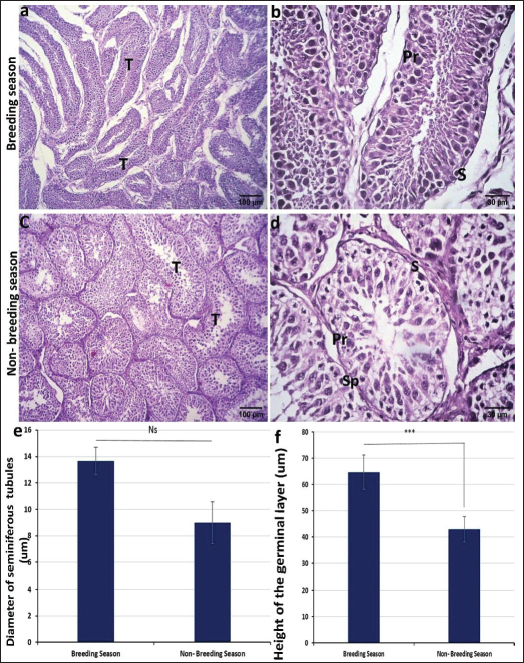

Histological examinationTo study the differences in histological structure during the fluctuations from the breeding season to the non-breeding season, testes were collected at different time points from December to March (breeding season) and from early June to late July (non-breeding season). The testis was divided by dense connective tissue septa into lobules containing seminiferous tubules where the sperms are produced. These tubules were more elongated in the breeding season (Fig. 2a) and round or oval in shape during the non-breeding season (Fig. 2c). The mean diameter of these tubules was larger in the breeding season than in the nonbreeding season, which is statistically insignificant (Fig. 2e). These seminiferous tubules were lined by stratified germinal epithelium composed of several phases, such as round spermatogonia with round dark nuclei, huge primary spermatocytes with enormous spherical nuclei, secondary spermatocytes, and spermatids. Sertoli cells can also be found in seminiferous tubules, which are oval or pyramidal in shape and positioned in the basal portion of the cell with ovoid nuclei (Fig. 2b and d).

Fig. 2. Photomicrograph of H and E stained section of ram testis during breeding season (a and b) and ram testis during non-breeding season (c and d); showing seminiferous tubules “T”, spermatogonium “SP”, primary spermatocytes “Pr”, and sertoli cells “S”. Morphometrical analysis of seminiferous tubule diameters and germinal layer thickness (e and f). Data are presented as mean ± SE. Ns, non-significant; *** highly significant p < 0.001. Histomorphometry revealed a highly significant difference (p < 0.001) in the germinal epithelium thickness between the breeding and non-breeding seasons. The interstitial tissue among the seminiferous tubules contains loose connective tissue and interstitial Leydig cells (Table 5). Table 5. Histomorphometry measurements representing the mean ± SE of seminiferous tubule diameter, germinal layer thickness, number of AR-positive Sertoli cells/tubule area, number of AR-positive myoid cells/tubule area, and number of S100 protein-positive cells per seminiferous tubule.